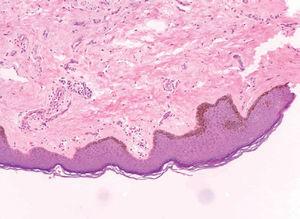

Presentamos el caso de un paciente de 29 años de edad, sin antecedentes personales de interés, que acude a nuestra consulta por presentar máculas multifocales heterocrómicas localizadas en el pene, completamente asintomáticas y que tiene desde los 14 años de edad. Desde entonces el paciente refiere que le han ido surgiendo nuevas lesiones pigmentadas con diversos tonos oscuros (fig. 1). En el estudio histológico se aprecia una hiperpigmentación de la capa basal, sin incremento en el número ni atipias de melanocitos (fig. 2).

Figura 2. Hiperpigmentación de la capa basal, sin aumento de atipias ni de melanocitos (hematoxilina-eosina, x100).

La histología confirma la naturaleza benigna del cuadro. Se caracteriza por acantosis sin elongación de las crestas interpapilares, hiperpigmentación de la basal sin aumento en el número de melanocitos (por lo que no deberían denominarse lentigos), incontinencia pigmentaria y presencia ocasional de melanófagos, todo ello en ausencia de atipias melanocíticas2.